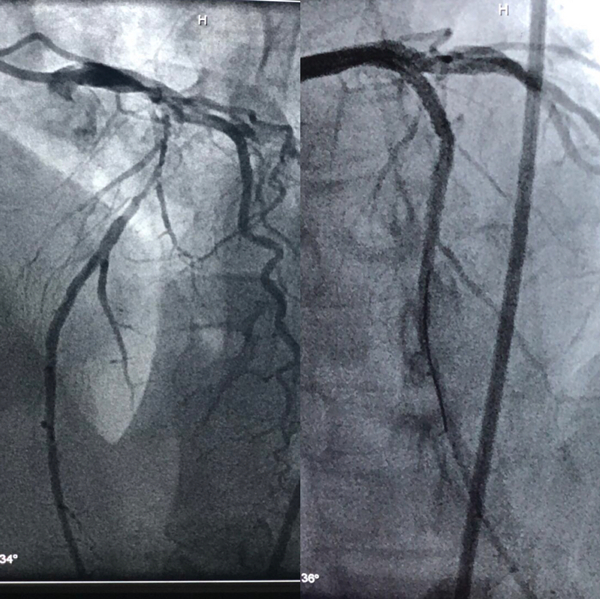

67岁的尹女士两年来反复发作胸闷、胸痛、气短,口服药物症状不能缓解。为求进一步诊治来我院急诊行CAG(冠状动脉造影术)检查,结果提示为:左冠脉走形区内可见明显钙化影。心脏血管左前降支近中段呈90%节段性狭窄,左回旋支近段狭窄90%局限性狭窄,中段后次全闭塞。右冠脉中段50-60%弥漫性不规则狭窄,其中以前降支钙化最为严重。心血管病院郑强荪院长评估患者病情后发现心脏血管确实钙化严重,在狭窄病变处植入支架有一定的难度,决定先为尹女士施行冠脉旋磨治疗,打通血管后再完成支架植入。

5月7日下午,由邓捷主任医师、薛嘉虹副主任医师、万招飞主治医师、李青主治医师、张荣主管护师、段文娜护师组成的冠脉介入治疗团队为尹女士采用全新的冠状动脉旋磨术。在完善相关术前检查后,邓捷主任医师用娴熟的技术术中先为血管打通一个“隧道”,使用带有超高速旋转头的转头将冠脉钙化斑块碾磨成细小的微粒,将血管腔内的斑块消除。经过几次旋磨后,阻塞血管腔的钙化斑块被逐渐消除,被磨成极其微小的颗粒,随血液循环至血管远端并通过毛细血管床吸收,之后完成冠状动脉支架置入手术。植入支架后为其行冠状动脉血管内超声发现血管狭窄解除,效果显著。

手术时间总共用时2个多小时。手术顺利,术后患者情况良好。在支架置入手术之前行冠状动脉斑块旋磨术,有助于获得理想的支架扩张效果,保证支架的充分扩张和良好的贴壁,有利于保持药物洗脱支架药物释放系统和聚合物的完整性,最终有利于降低支架内再狭窄和支架血栓的发生率。冠状动脉旋磨术技术难度高,因为术中有可能出现冠脉穿孔、血压低等风险。手术操作非常精细,对手术操作者的手术技巧及心理素质要求极高。心血管病院成功开展这一新技术,标志着在复杂冠脉病变的介入治疗水平又上了一个新的台阶。